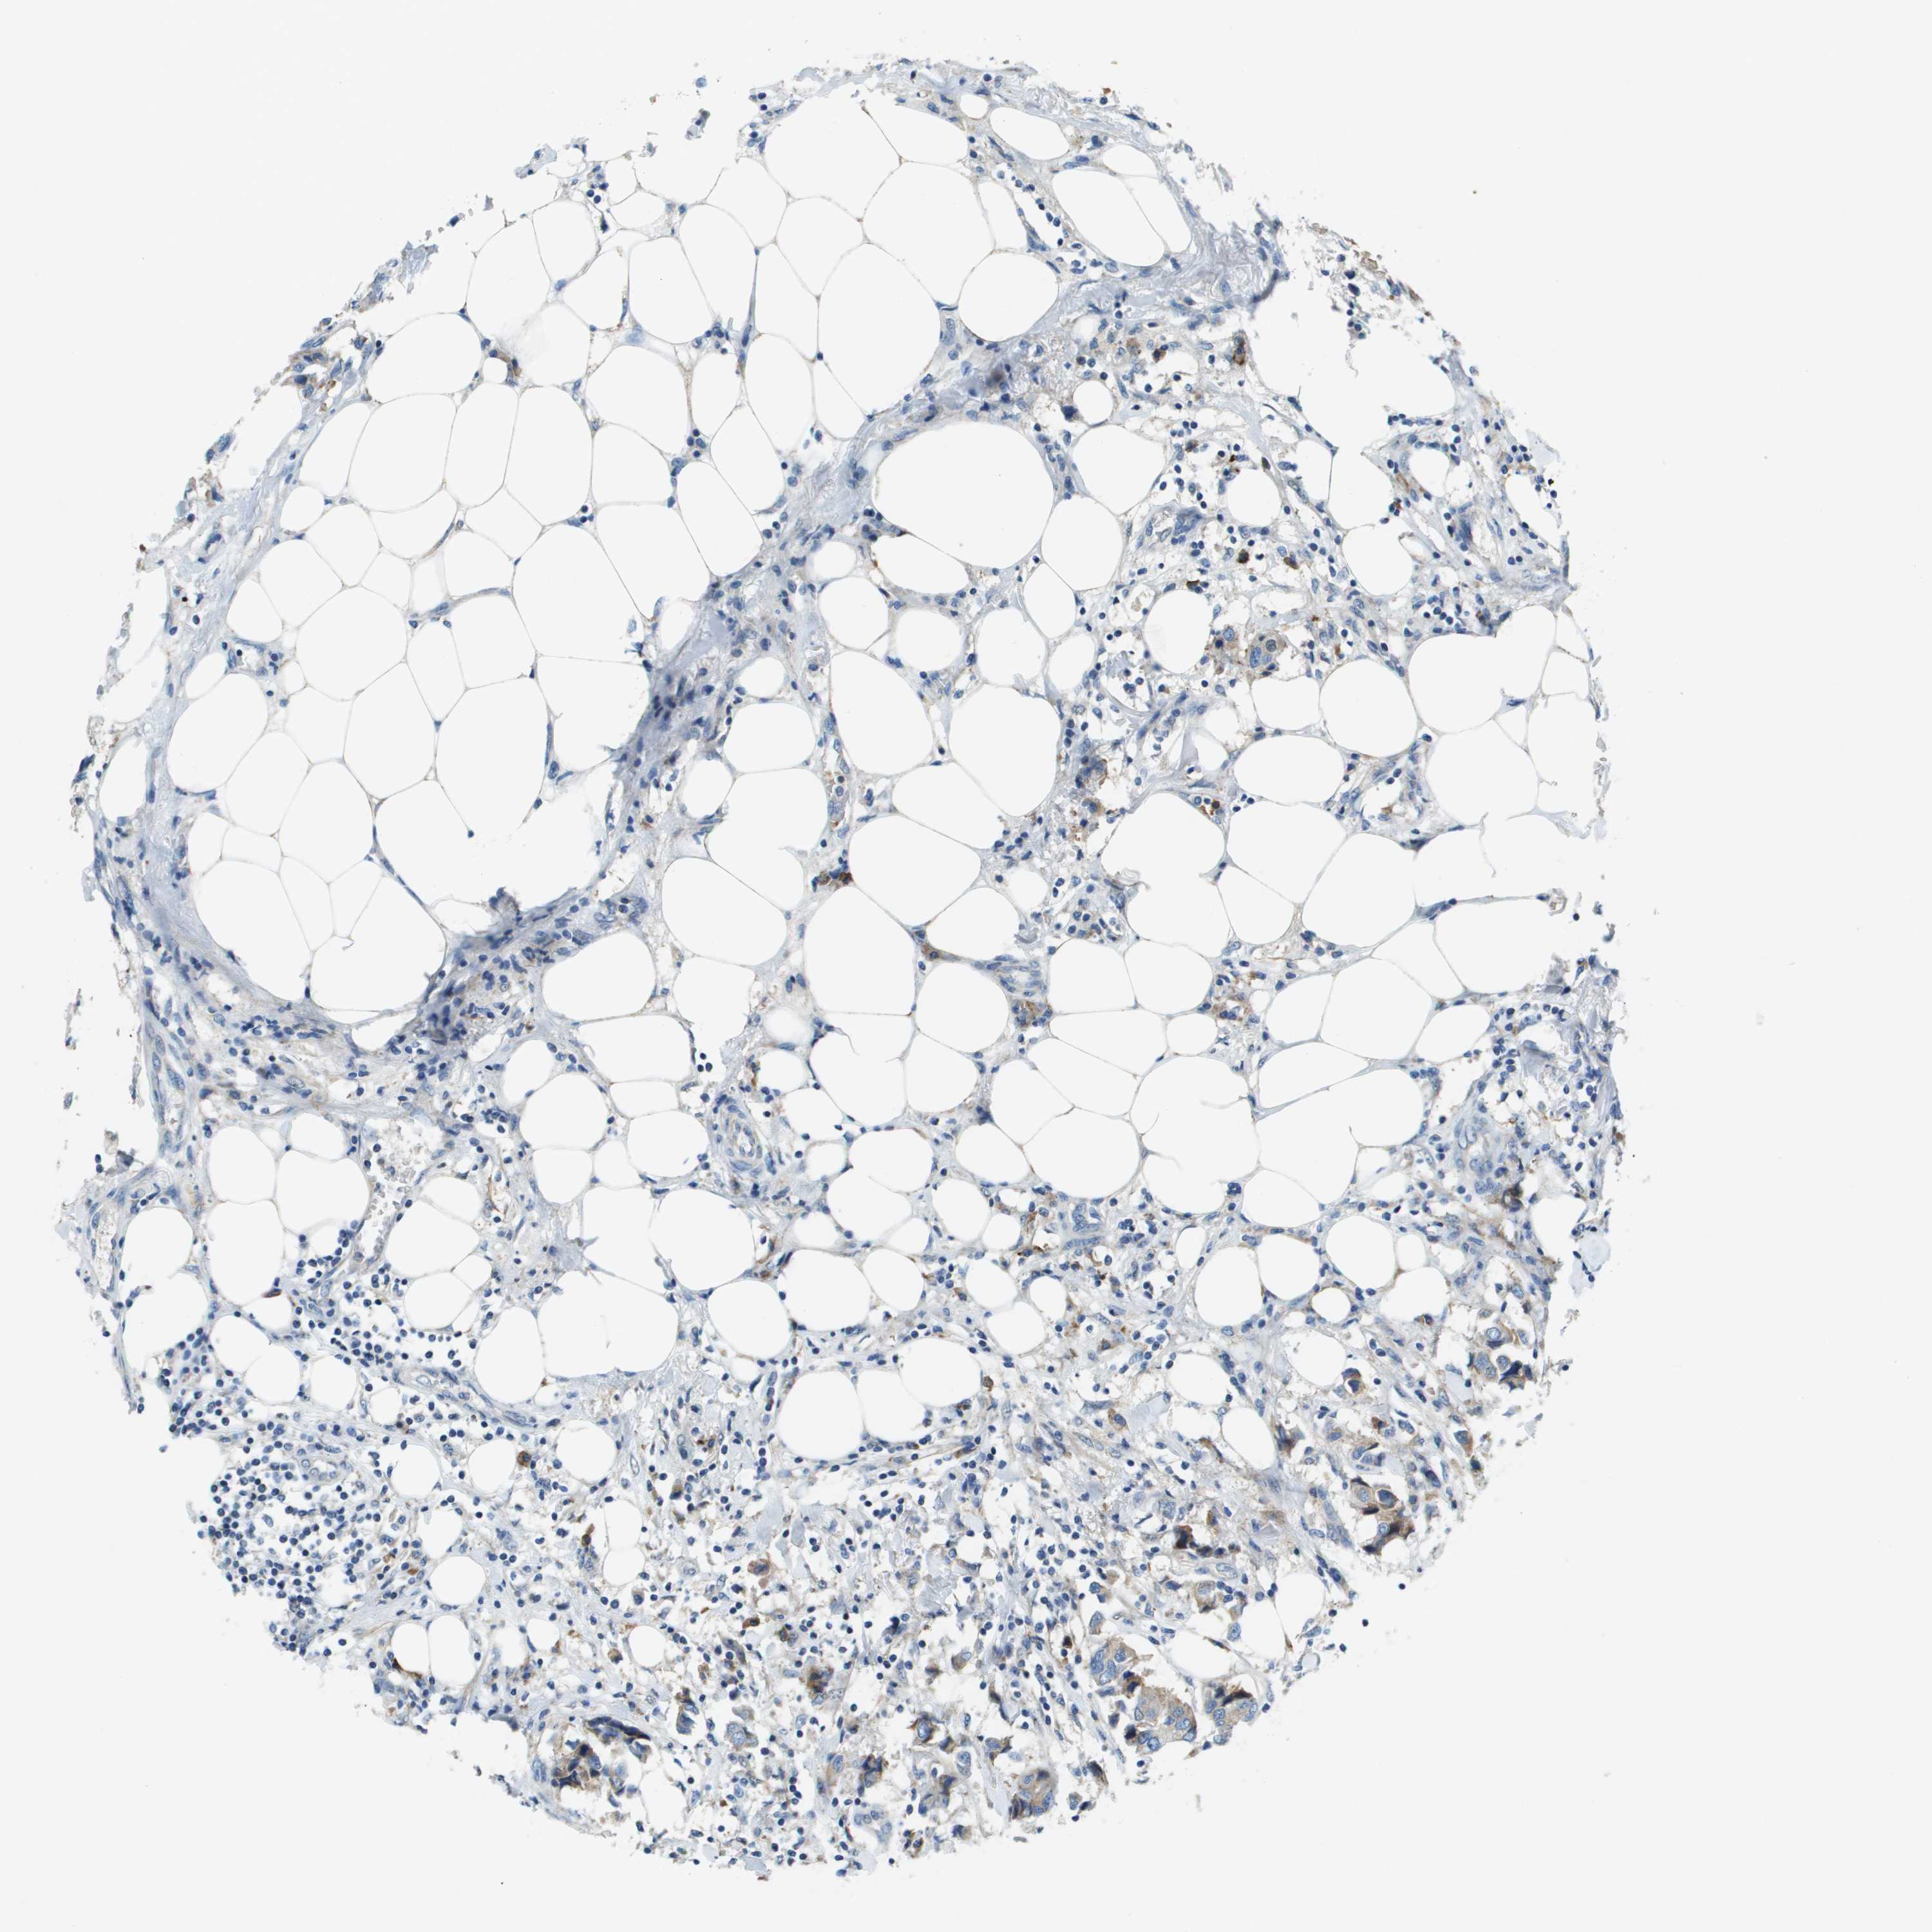

BRCA TCGA BRCA VALIDATION PROTEIN EXPRESSION

ANTIBODIES

AND

VALIDATION